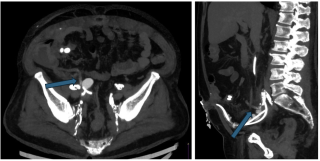

Case presentation

A 65-year-old woman with rectal adenocarcinoma (pT4bN0R2, KRAS-mutated) treated with neoadjuvant chemoradiotherapy, and extensive pelvic surgery developed chronic right-sided ureteral obstruction requiring long-term ureteral stenting. From 2023 onward, she experienced recurrent episodes of pyelonephritis, with urine cultures repeatedly isolating enteric organisms. In 2025, pelvic magnetic resonance imaging and retrograde ureteropyelography revealed right-sided hydronephrosis and a fistulous tract connecting the distal right ureter and the rectosigmoid colon, without evidence of tumor recurrence. Surgical management consisted of a bloc resection of the fistula, proctectomy with perineal closure, right ureteral reimplantation, terminal colostomy, and omentoplasty. The postoperative course was uneventful.